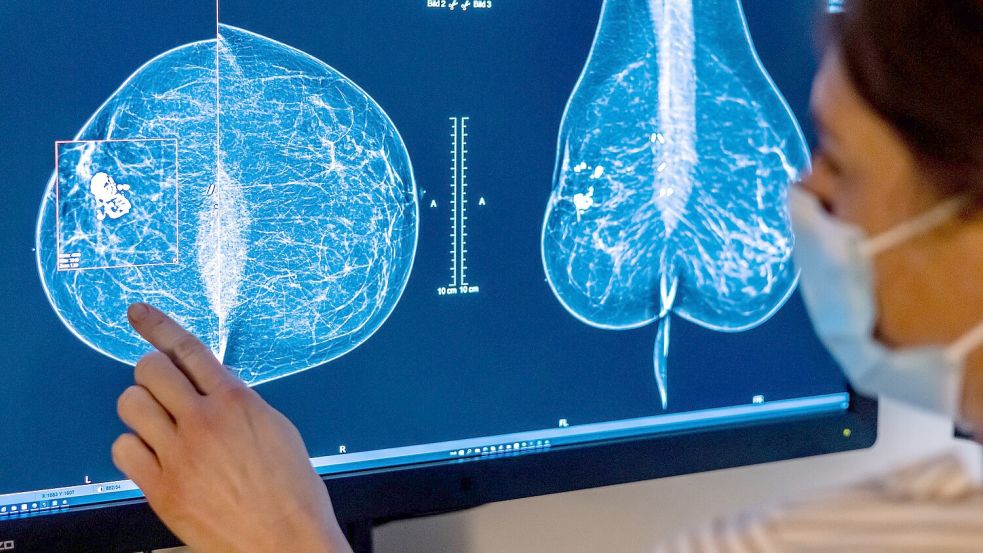

Im Jahr 2023 wurden demnach bei rund einer halben Million Menschen in Deutschland eine Tumorerkrankung neu diagnostiziert. Von diesen 517.800 Krebserkrankungen traten rund 276.400 bei Männern und etwa 241.400 bei Frauen auf. Etwa die Hälfte aller Neuerkrankungen betrafen die Prostata (79.600), die Brustdrüse (75.900), die Lunge (58.300) oder den Dick- und Enddarm (55.300).